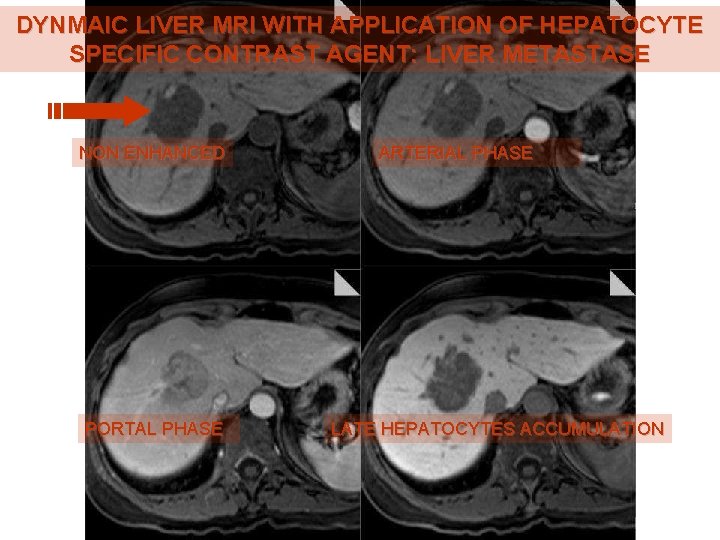

DYNMAIC LIVER MRI WITH APPLICATION OF HEPATOCYTE SPECIFIC CONTRAST AGENT: LIVER METASTASE NON ENHANCED PORTAL PHASE ARTERIAL PHASE LATE HEPATOCYTES ACCUMULATION